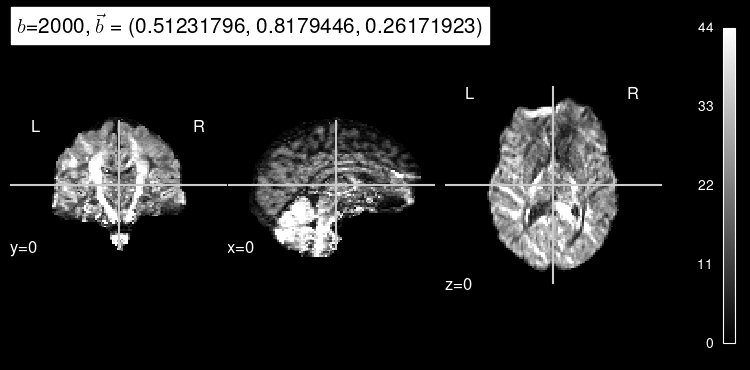

Here’s the original DW map, for reference:

plot_dwi(test_data, dmri_dataset.affine, gradient=test_b);

plot_dwi(predicted, dmri_dataset.affine, gradient=test_b, black_bg=True);